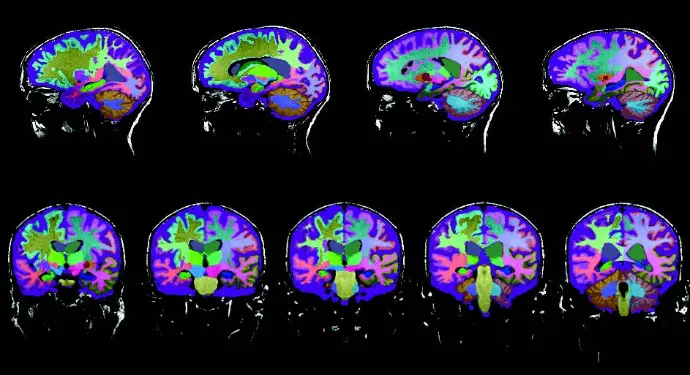

Report generation timing is essential for workload, workflow optimization and for prompt diagnosis in clinical settings. On average, US radiologists typically spend around 24 minutes reviewing a brain MRI and drafting a report [1,2]. That said, Neuroreader® reduces the time required to read an MRI from 24 minutes down to 10 minutes or less (by a cloud-based data analysis computer program). With advanced deep learning techniques, the computer program can visualize and quantify a large number of brain structures. Neuroreader® objectively analyzes DICOM images from MRI brain scans by comparing the patients brain volumes against a normative database with people of similar age, gender and head size. It measures and identifies atrophies of brain structures, such as the hippocampus, lateral ventricles, and brain lobes.

Often, when discussing controls of cognitive impairment and neurodegenerative diseases in general, the dissimilarity coefficients are very high, typically around 88%. This number typically holds across all types of cognitive decline. The reason why that is important is that if comparing the automated volumetric segmentation with Neuroreader® to the so-called gold standard anatomical segmentation by an expert anatomist, there is a high degree of agreement between the two methods. Except with volumetrics, you have a very high, thorough, and accurate segmentation in a short time-period, as hand drawn, manual segmentations typically take a lot longer. [7] This ultimately means that the speed of clinical decision-making is a lot faster when using an automated volumetric segmentation method like Neuroreader®, resulting in earlier diagnosis, adequate, and faster patient care.

With automated volumetric data of brain MRI, you gain insights where the atrophy is occurring in the brain, which specific brain regions are affected, and which are not, as well as the magnitude to which they are affected. Furthermore, it gives us information about the progression. In comparison to manual hippocampal tracing, Neuroreader® can compute the volume of the hippocampus in less than five minutes and multiple structures of the entire brain in less than 10 minutes.